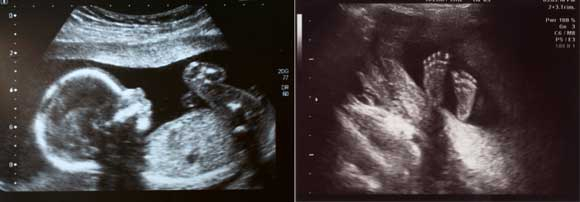

Many abortion providers have been converted by ultrasound technology. The most famous example is Bernard Nathanson, cofounder of the National Association for the Repeal of Abortion Laws, the original NARAL. By his own reckoning Nathanson performed more than 60,000 abortions, including one on his own child. But over time he began to fear he was involved in a great evil. Ultrasound images pushed him over the edge. “When he finally left his profession for pro-life activism, he produced The Silent Scream (1984), a documentary of an ultrasound abortion that showed the fetus scrambling vainly to escape dismemberment.”